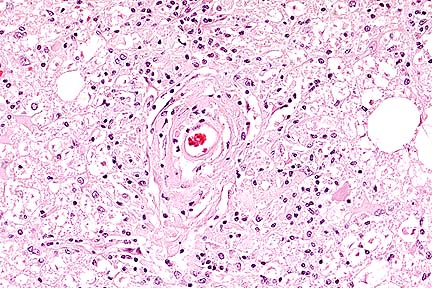

Acute ulcerative colitis in a foal treated with castor oil (HE, 200X, 50K).

Contributor's Diagnosis and Comments: Colitis, severe, focally extensive, acute, erosive and necrotizing. Castor oil-induced superficial colitis, with secondary probable endotoxin-induced submucosal thrombosis, inflammation, and mucosal necrosis.

A large area of the submucosa is thickened by edema, hemorrhage, acute inflammatory cell infiltration, lymphatic distention and venous and capillary thrombosis. The overlying mucosa in necrotic, and there are multiple surface clumps of bacteria. Adjacent viable areas of mucosa have flattened superficial epithelium, inflammatory cells between membrane and epithelium and capillary thrombosis. Severe hemorrhagic foci are present in the muscularis and serosa.

Acute superficial enterocolitis is reported in the literature following the experimental administration of castor oil to ponies. In the cecum and ventral colon, there is extensive erosion of superficial epithelium between crypts, with fibrin, neutrophils and cell debris on the denuded basement membrane. By 48 hours post ingestion, there is partial restitution of surface epithelium by flattened epithelial cells extending from the necks of crypts. Fragmented necrotic debris is sometimes present within macrophages within the lamina propria. Mucosal venules beneath the erosions are plugged with fibrin, and there is general mucosal venous congestion and distention of submucosal lymphatics.

In the equine gastrointestinal system, transit is rapid from stomach to cecum to ventral colon, but slow from ventral colon to dorsal colon, allowing prolonged exposure to toxic components. The toxic component of castor oil is ricinoleic acid. The full thickness necrosis of the mucosa and the severity of the submucosal lesion in this case suggest additional factors were operating as well as castor oil. After uncomplicated poisoning by castor oil, it is reported that repair of the mucosa is complete by 72 hours post-dosing.